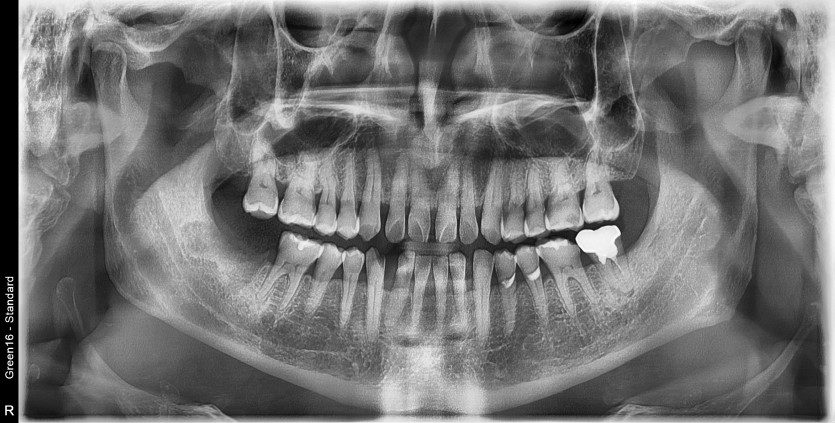

#48 사랑니 발치

구강 외과 전문의가 당일 발치했습니다.